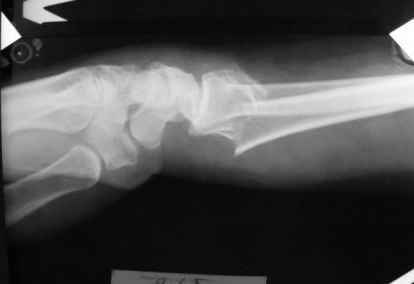

Уважаемые коллеги.Прошу обсудить случай лечения перелома дистального метаэпифиза

лучевой кости. Ситуация скандальная и крайне неблагоприятная.

15.12- перелом луча в Москве. Там же репозиция, гипс. Дальнейшее

лечение у нас в ЦРБ. 20.12.- вторичное смещение в гипсе

21.12- под внутривенным наркозом - репозиция, гипсовая лонгета.

Объективно говоря- снижена высота лучевой кости, диастаз лучелоктевого сочленения, и не

сросся шиловидный отросток. однако на РКТ при сравнении с другой стороной- разница

незначительная.

1.Прошу объективно оценить качество нашей репозиции на момент 21.12. (неужели так плохо?).

Что на снимках при снятии гипса- сам вижу.